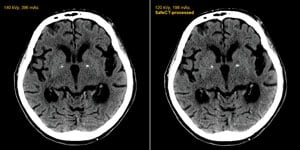

Figure 2 From Low Dose Ct Scan Screening For Lung Cancer Comparison Of Images And Radiation Doses Between Low Dose Ct And Follow Up Standard Diagnostic Ct Semantic Scholar